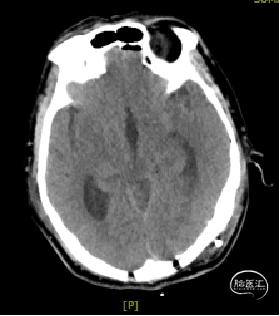

术后1天复查CT

术区无出血,脑室系统较术前显著缩小,脑积水缓解。